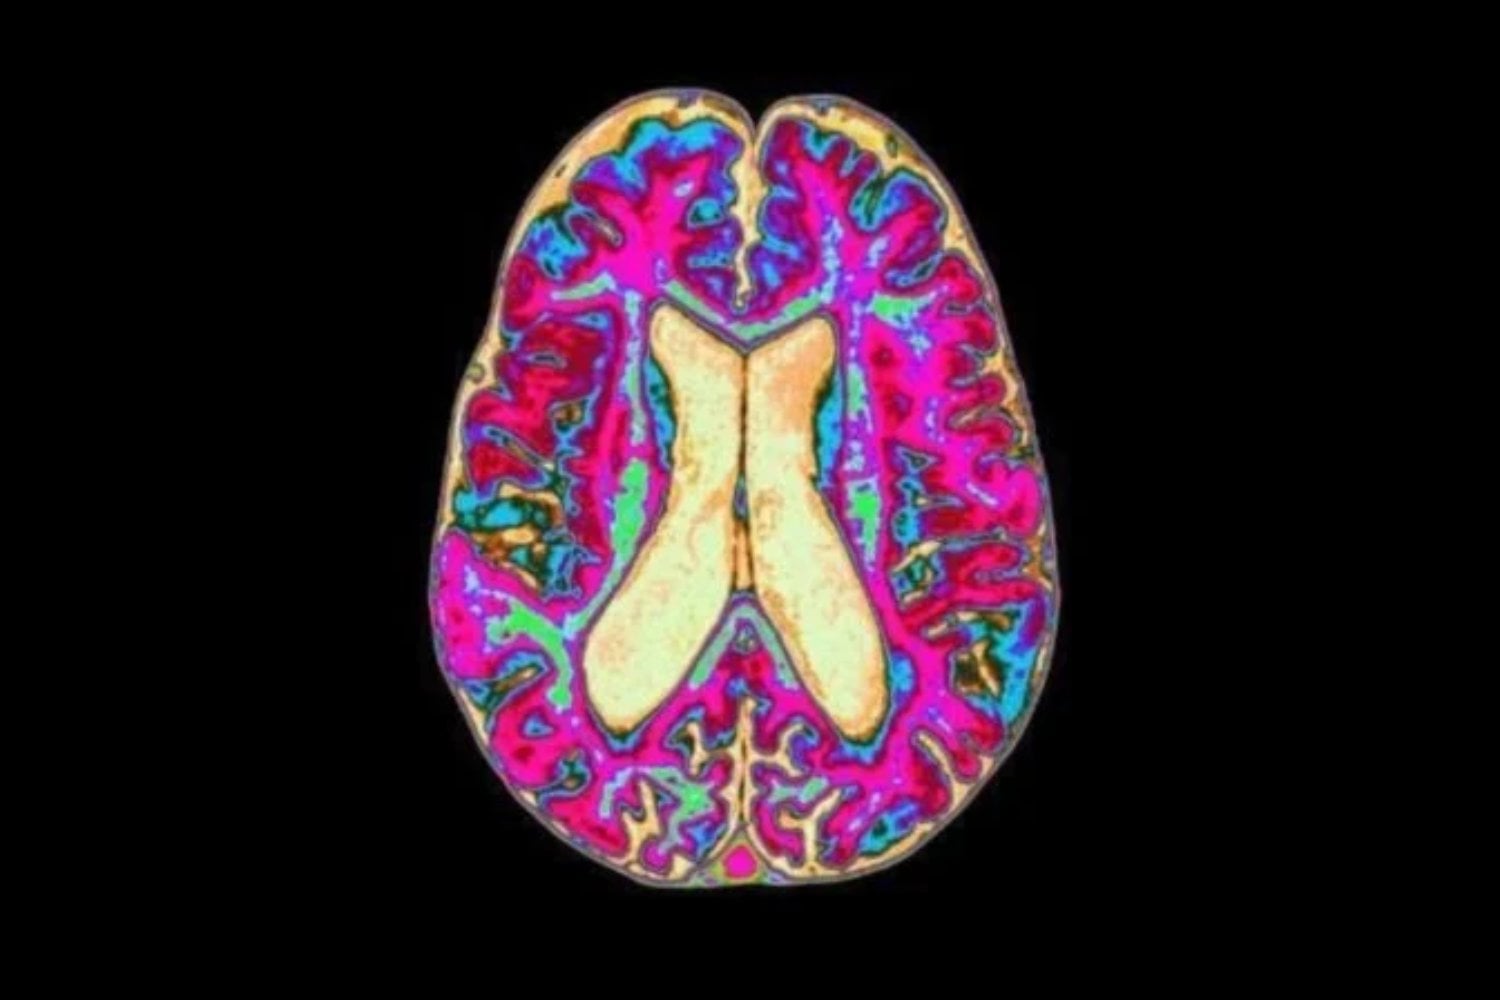

El neurólogo Bill Langston descubrió que no era un caso aislado: había más “adictos congelados” en el área. Todos se habían inyectado una droga mal sintetizada. En lugar de la sustancia esperada, recibieron MPTP, un compuesto que destruye neuronas dopaminérgicas en una región clave del cerebro: la sustancia negra.

Cuando Langston lo probó en primates, la evidencia fue brutal: el químico podía provocar un cuadro indistinguible del Parkinson. Por primera vez, había una prueba sólida de que una sustancia ambiental podía causar Parkinson. Era una revolución. Y aun así, el campo científico no se volcó masivamente hacia ahí. Porque en los 90 llegó otro imán: el Proyecto Genoma Humano. La genética se volvió “sexy”, financiable, prometedora. Y la hipótesis ambiental perdió oxígeno.